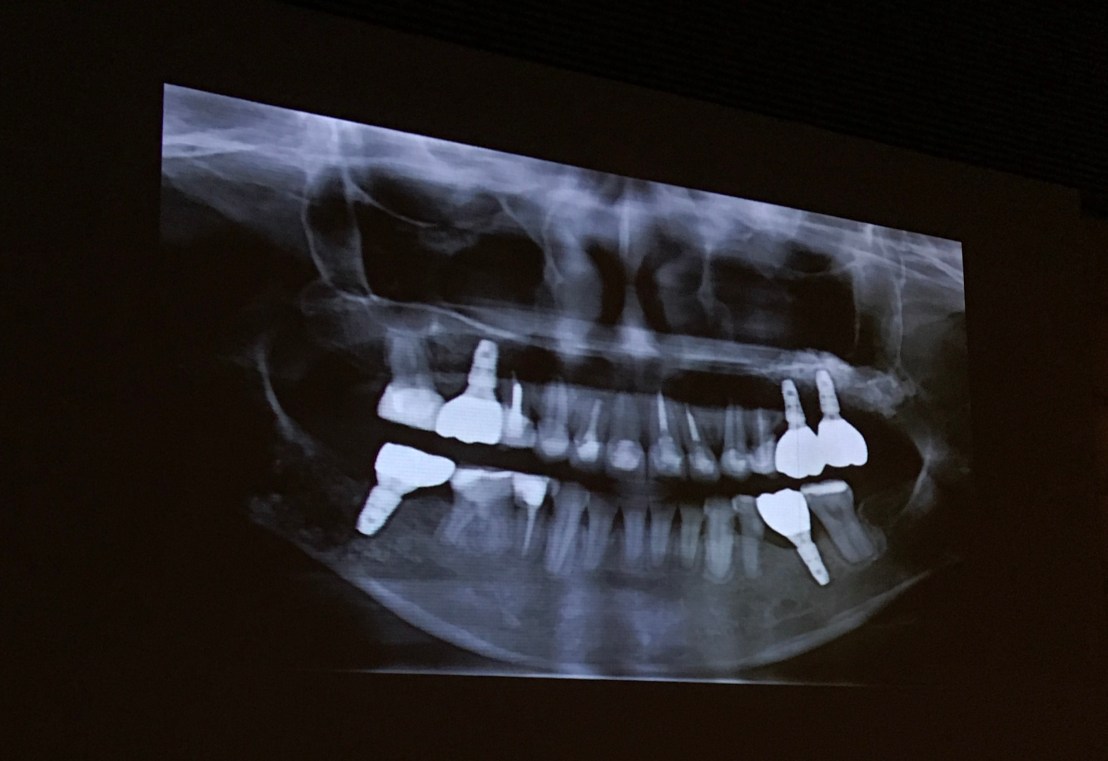

ฝัง Implant ใหม่ร่วมกับ Ortho

OPG Final pros